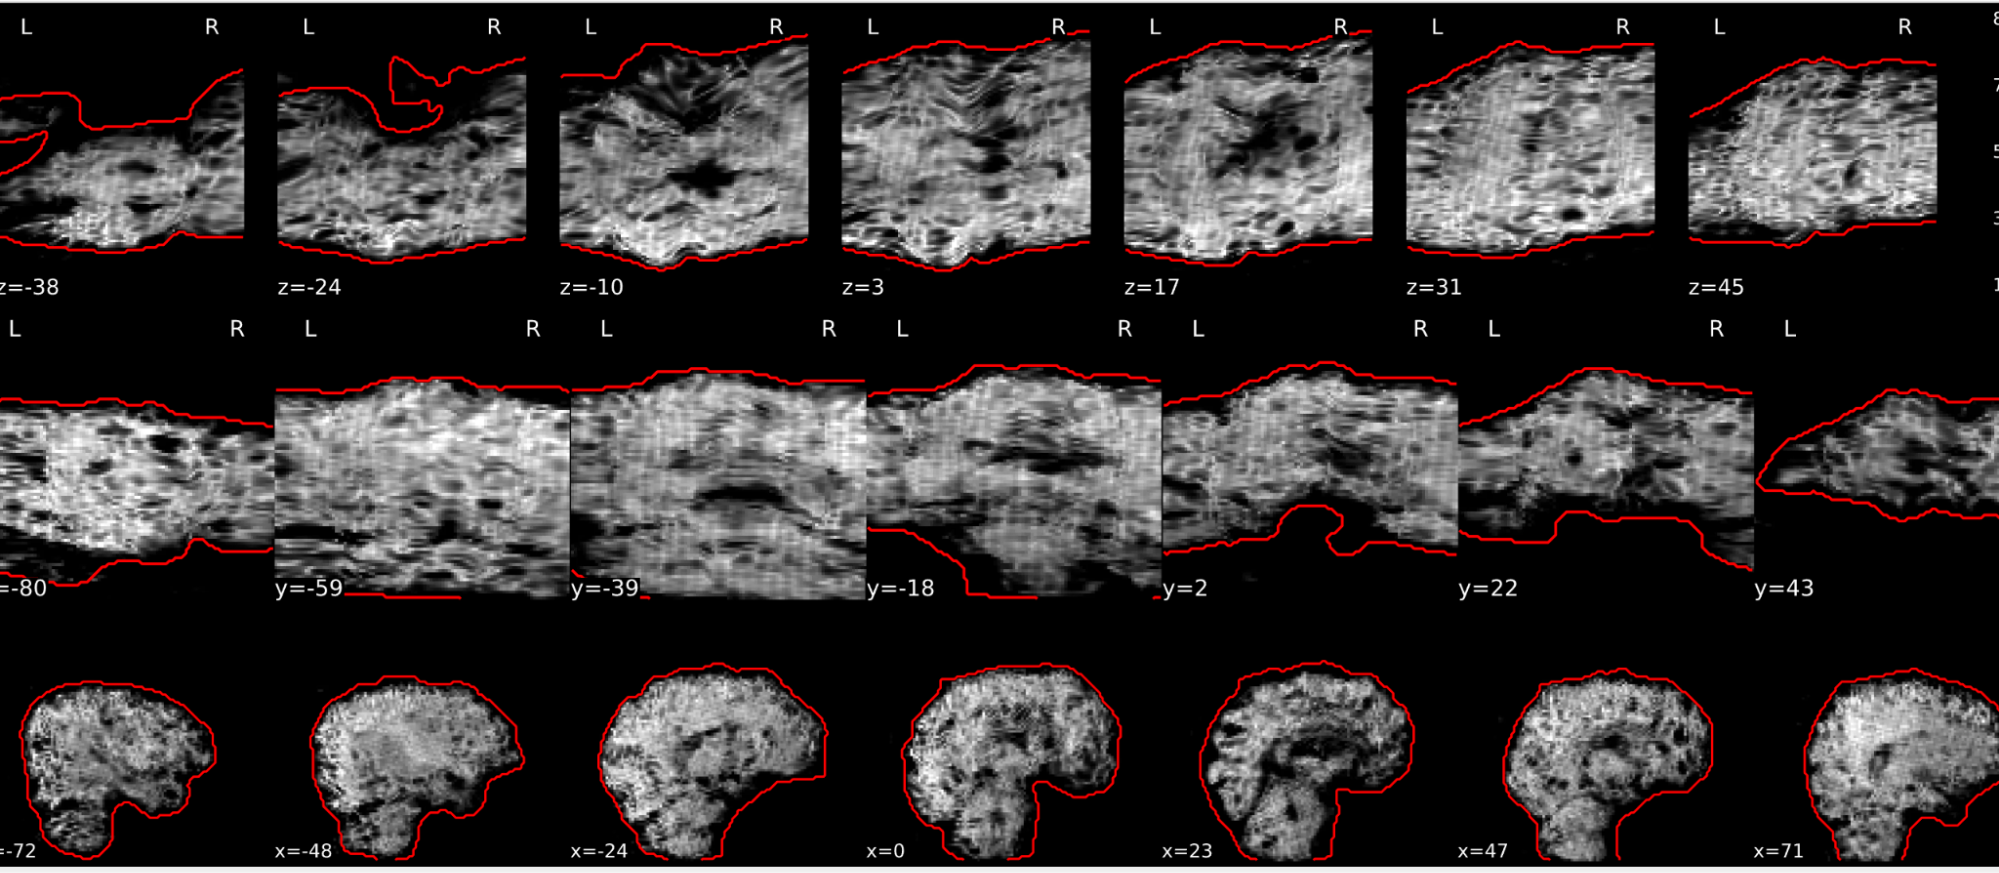

EPI ICA-based artefact removal

The fMRI data for each subject are decomposed into spatially independent components. Each component is represented by a spatial map and a time course. Some components represent noise, some signal. ICA AROMA is trained to automatically classify these components. Signal components are usually represented by low numbers of large clusters (some of which may represent known networks such as the Default Mode Network), located in the GM and away from WM, CSF, blood vessels, or the edges of the brain. Signal components usually do not have a particular shape, while noise components may show banding or ring patterns. Signal components usually have low frequency (0.01-0.1 Hz) (i.e., few spikes on the left hand side of the power spectra plot), while noise high frequency, or very low. The time series of signal components is oscillatory and fairly regular, while in noise we may see sudden spikes or differing patterns (see Griffanti et al., 2017. Hand classification of fMRI ICA noise components. NeuroImage).

Some examples are presented below. For each component, there is a spatial map (on the left), the time series (top plot on the right) and the power spectra (bottom plot on the right). Of note, ICA AROMA errors cannot be ‘fixed’, as it automatically classifies the components.

We don’t expect you to check all the components for every subject. Rather, try to eyeball the report and see whether generally clusters that should be signal (according to the description above) are coloured in green. If you think that ICA AROMA performed poorly, check the other quality metrics for that subject to decide whether they should be excluded.

Example of a good subject

- Components correctly classified in noise (red) and signal (green), conservative classification (uncertain components classified as signal).

Example of a bad subject

- ICA AROMA might have performed poorly if it classified all/most of the components as noise, when some of them could have been signal. These types of errors are more likely to occur in task fMRI with block designs, whereby some task-related activity may be classified as motion. In resting state, try to look for common large brain networks such as the default mode network/salience network. If they have been classified as noise, ICA-AROMA might have not performed well. It is possible that ICA AROMA classified all/most of the components as noise if the subject was particularly problematic (lot of motion, artefacts)

- Components that look like rings, bandings or stripes are usually acquisition-related artefacts (e.g., interleaved acquisition, multi-band). The presence of these artefacts is not an issue by itself, but ideally these components should be classified as noise. Note that ICA AROMA was not trained on multiband data, so it is possible that it classifies some of these components as signal (nothing we can do about).

- We don’t expect you to check all the components for every subject. Rather, try to eyeball the report to get a general idea. If unsure, and there is a recurring issue across youdr dataset, please send us some screenshots.

- In case of uncertain components, it is preferable that ICA AROMA behaved conservatively, and did not remove these components, because they may contain some signal

NOTE: If you think that ICA AROMA performed poorly or the subject looks problematic, check the other quality metrics for that subject to decide whether they should be excluded.

Summary

| good | bad |

|---|---|

| Time series (at the top): no sudden jumps power (bottom) | More noise (red) than signal (green): - Occurs more often with block design - or “problematic” subject (lots of movement, lots of artefacts) rings, bands, artefacts - should be classified as noise |

| Spatial patterns are visible | |

| No sudden jumps/spikes | |

| No big spikes |